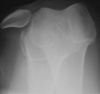

You order frontal, lateral, and sunrise radiographs of the right knee. What do these films reveal about the extent of this patient’s injury?

Knee pain following a soccer injury: The frontal radiograph reveals that the patella is dislocated laterally (A). This is confirmed on the sunrise radiograph (B). A lateral radiograph shows the malalignment of the patella with the distal femur (C). Most important, it also shows no fracture. Lateral dislocation of the patella is diagnosed.